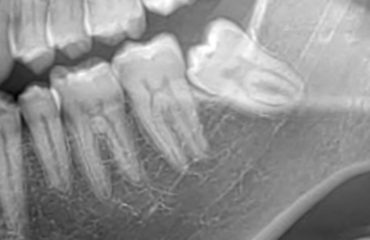

La parodontite o piorrea è una delle malattie più diffuse al mondo ed è caratterizzata da un’infiammazione cronica causata da microrganismi specifici che si trovano nella placca batterica che provoca, se non curata, la distruzione dei tessuti di sostegno dei denti (cioè del parodonto) e conseguentemente la loro perdita.La parodontite è una malattia che può […]